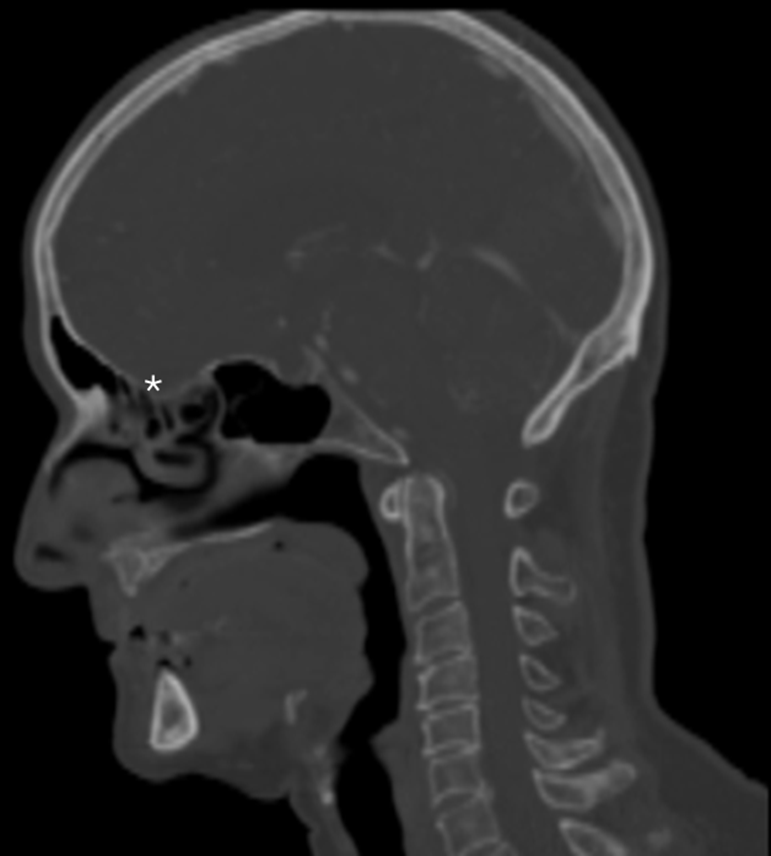

2.108 In einer radiologischen Darstellung (Sagittalschnitt) des Schädels ist ein weißer Stern im Bereich der vorderen Schädelgrube direkt über dem Dach der Nasenhöhle platziert. Welche anatomische Struktur wird durch diesen Stern markiert und welcher Nerv befindet sich da?

- (A) Canalis opticus – N. opticus (II)

- (B) Lamina cribrosa – Fila olfactoria (I)

- (C) Foramen rotundum – N. maxillaris (V2)

- (D) Meatus acusticus internus – N. facialis (VII)

- (E) Fissura orbitalis superior – N. ophthalmicus (V1)